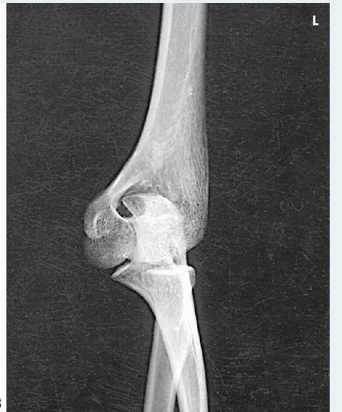

Which, from the following list of image criteria, is not met with this AP elbow image?

d.Arm is not extended

What is the corrective action required for a repeat AP elbow image when the patient cannot fully extend their arm?

a.Acquire 2 AP images, one for the proximal forearm, one for the distal humerus